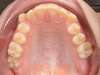

Avant

Après